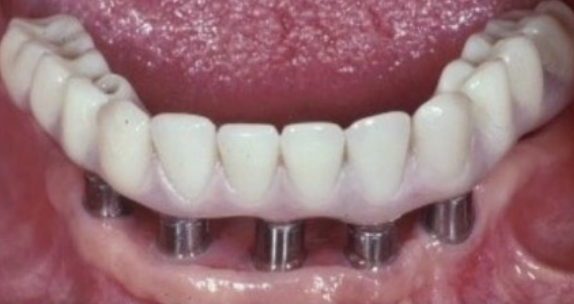

Many factors should be considered when designing implant-supported restorations to reduce the risk of peri-implantitis affecting physical removal of bacterial plaque at the FMG. Included are oral hygiene devices, accessibility, prosthetic shapes, and patient ability to comply with oral hygiene procedures. The design should be conveniently hygienic so patients can easily comply with the recommended oral hygiene procedures. Physical removal of bacterial plaque on the intaglio surface at and above the FMG reduces the risk of peri-implantitis in the sub-gingival transmucosal tissue around dental implants. The original fixed prosthetic design presented by Branemark, a "High water design", provided access to all surfaces for oral hygiene management without a patient complaint of food accumulation (Figure 9 and Figure 10). Notably, relief above the gingiva was not patient complaint with this design. Lack of embrasure access to the FMG and intaglio surfaces for oral hygiene management can lead to peri-implantitis (Figure 11 and Figure 12). Stein recommended a convex modified ridgelap pontic design with lingual and palatal access to facilitate plaque removal from the intaglio surface under pontics in fixed prosthetics with dental floss.20 These shapes should be standard for fixed implant-supported restorations whether individual or multi-unit restorations made of ceramo-metal or milled zirconia (Figure 13 through Figure 16).

Commonly available oral hygiene devices include manual and mechanical toothbrushes, irrigation devices, dental floss with threaders and proxi-brushes. To be affective, all devices must have access to reach the prosthetic-implant interface to remove the  oral biofilm. Rotary mechanical brushes may not reach the interface as well as straight bristles that can be directed to the interface. In areas difficult to reach, especially in multi-unit posterior restorations, 2 mm relief of the intaglio surface from the soft tissue provides improved access for toothbrush contact for plaque removal (Figure 17 and Figure 18). Water Flossers or Air Flossers without toothbrushing does not adequately remove oral biofilm.21,22 Dental floss with threaders when used properly are effective in disrupting the oral biofilm if the intaglio surface is convex and the patient has the necessary manual dexterity to thread the floss into those areas.

(13.) Prosthetic design allowing access to FMG interface.

Figure 13

(14.) Healthy Gingival Tissue.

Figure 14

(15.) FMG access and convex intaglio profile.

Figure 15

(16.) FMG access and convex intaglio profile.

Figure 16